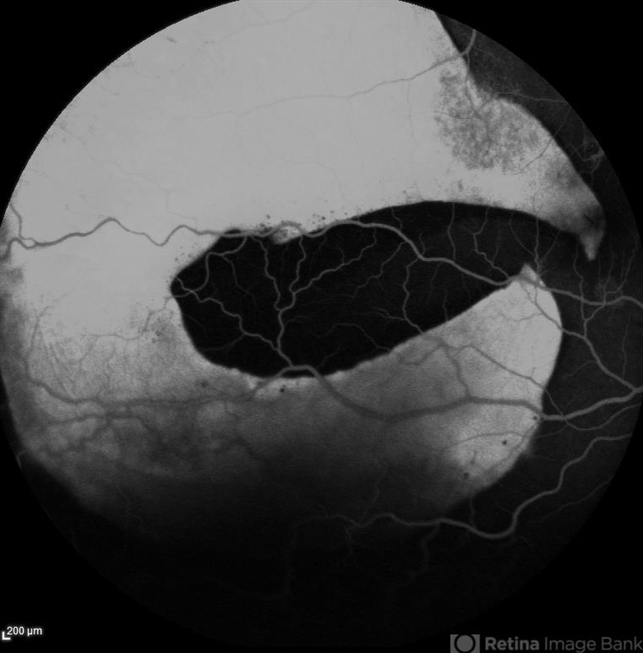

- RPE-Rip

Scanning laser ophthalmoscope

Heidelberg HRA - Description

- Fundus fluorescein angiography of a 50 year-old patient with spontaneous giant RPE rip.